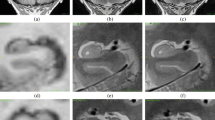

No major segmentation errors were found upon visual inspection. Figure 2 shows hippocampal segmentation results overlaid on the corresponding T1 from a sample subject.

Illustration of the hippocampal subfield segmentations in sagittal (top left), axial (bottom), and coronal (top right) views. Subfield structures of a sample subject (site 1, session 1, longitudinal pipeline with FLAIR) are overlaid on the corresponding averaged T1-weighted image generated by FreeSurfer 6.0 during the automated processing. The images were made using the FreeView visualization tool (https://surfer.nmr.mgh.harvard.edu/fswiki/FreeviewGuide/). CA1, CA2-3, CA4 cornu ammonis areas, GC-ML-DG granule cells in the molecular layer of the dentate gyrus, HATA hippocampal-amygdala transitional area, Hp_ML molecular layer, Fissure hippocampal fissure, Hp_Tail hippocampal tail